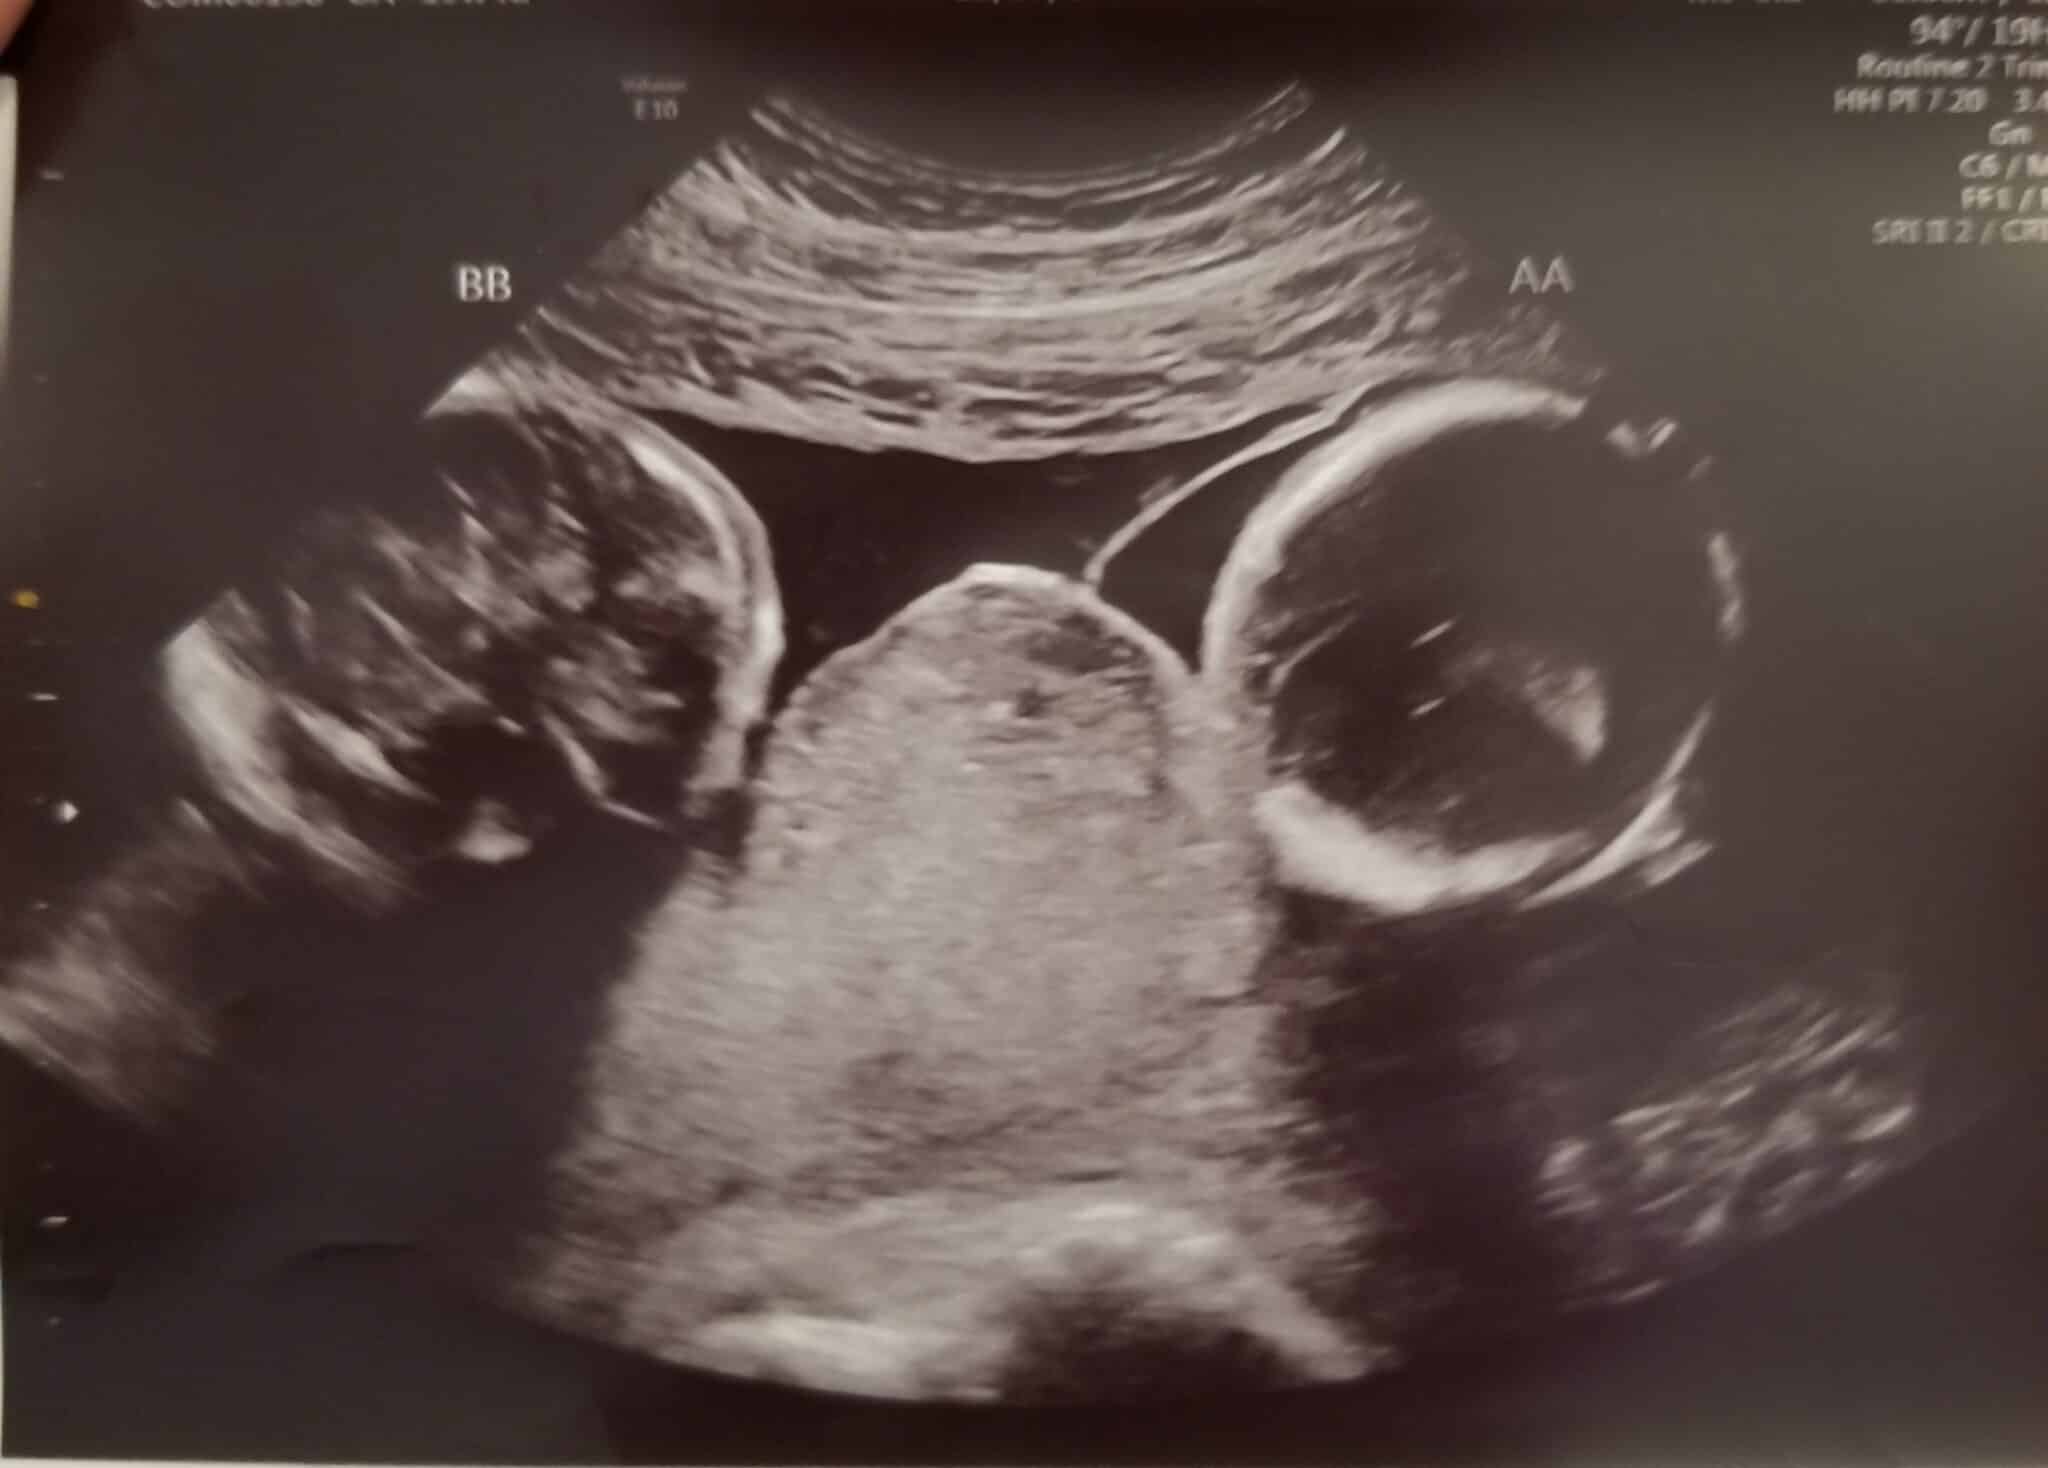

Ultrasound Photos at 19 Weeks Pregnant With Twins